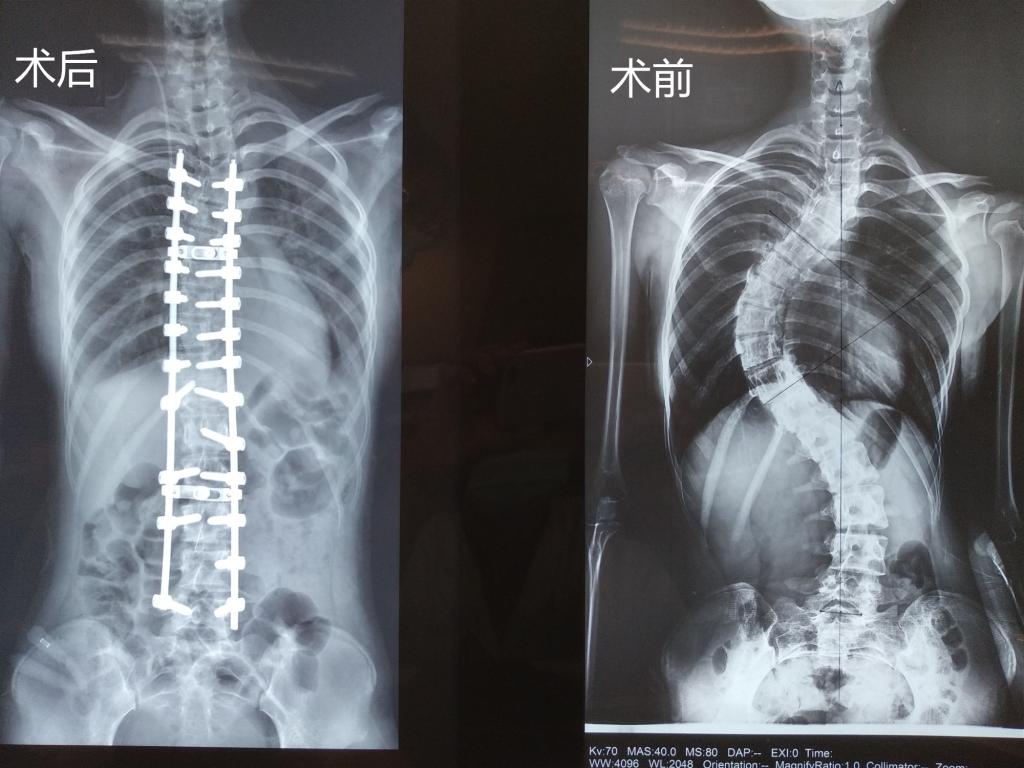

據(jù)我院脊柱骨科主任胡朝暉介紹,小孔來院檢查時(shí)脊柱側(cè)凸畸形非常嚴(yán)重,已經(jīng)對(duì)女孩的日常生活造成了嚴(yán)重影響,且畸形極可能進(jìn)一步加重,壓迫心臟、肺、腹部等臟器,引起呼吸困難等心肺腹問題,還可能會(huì)出現(xiàn)頑固性背痛、站立和行走困難、跛行、肢體無力、大小便失禁等癥狀,必須通過手術(shù)對(duì)其脊柱側(cè)凸畸形進(jìn)行矯形、固定。

“患者椎骨結(jié)構(gòu)異常,椎體旋轉(zhuǎn),椎弓根細(xì)小,均會(huì)導(dǎo)致術(shù)中置釘難度大大增加,且患者患者肺功能已受限,手術(shù)矯形后,兩肺空間重新分布,兩側(cè)胸腔大量積液會(huì)加重呼吸困難、甚至危及生命……”面對(duì)這一系列的困難,脊柱骨科醫(yī)療團(tuán)隊(duì)為小孔設(shè)計(jì)了多套應(yīng)急預(yù)案,做好充分準(zhǔn)備來應(yīng)對(duì)可能出現(xiàn)的所有情況,確保手術(shù)萬無一失。

幾天后,脊柱骨科醫(yī)療團(tuán)隊(duì)頂著巨大的精神壓力為小孔進(jìn)行脊柱側(cè)彎矯正術(shù),術(shù)中置入26枚螺釘,歷時(shí)近7小時(shí),手術(shù)非常成功,麻醉清醒后,小孔的雙腿可以自如活動(dòng),此刻包括胡朝暉主任在內(nèi)的所有醫(yī)護(hù)人員都打心眼里為她高興。

術(shù)后恢復(fù)期,護(hù)理團(tuán)隊(duì)密切配合,精心呵護(hù),小孔的狀態(tài)一天比一天好,當(dāng)她第一次下地活動(dòng),驚喜地發(fā)現(xiàn)自背竟然挺起來了!醫(yī)務(wù)人員告訴她,她足足長(zhǎng)高了6公分!小孔激動(dòng)得眼淚都要掉下來了:我的生活終于回歸正常,感謝各位叔叔阿姨!